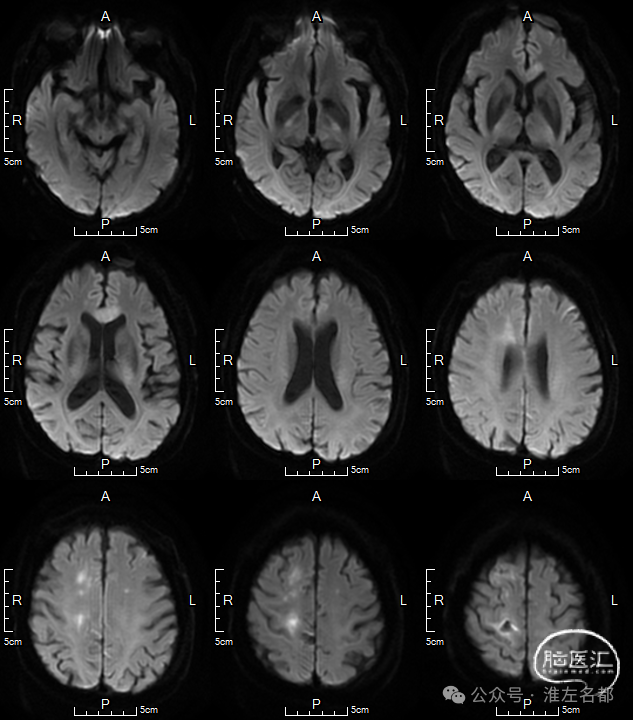

2024-01-23 MRI

DWI:胼胝体膝部和右侧额顶叶皮质多发急性梗死高信号。

SWI:右侧额顶叶皮质梗死灶渗血低信号;前纵裂池内可见少量蛛网膜下腔出血低信号。

3D-TOF-MRA:右侧大脑前动脉A2段管腔未见明确异常。